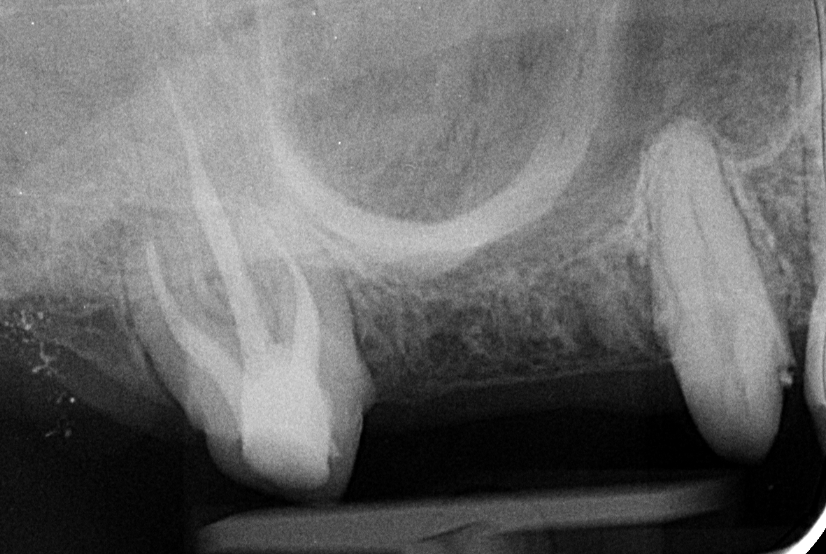

Dr. Sápi Béla páciense a hiányzó jobb felső első nagyőrlőjét szerette volna pótoltatni, és a szakvéleményt figyelembe véve a hídpótlás mellett döntött. A fémkerámia pótlások esetében egy belső kobalt-króm ötvözet adja a belső, merev vázat, amely cementtel rögzül a fogra (vagy a fogakra), és erre kerül ráégetéssel az esztétikus, fogszínű kerámia. A fémkerámia pótlás előnye, hogy költségkímélőbb a többi pótlással szemben, és ezzel a hagyományos módszerrel is tartós és esztétikailag kielégítő pótlások készíthetőek.

Bár a pótláshoz megoldásképpen akár az implantáció is szóba jöhetett volna, a vizsgálatokból és a röntgenfelvételekből az derült ki, hogy az implantátum behelyezéséhez az alacsonyan elhelyezkedő arcüreg miatt csontpótlásra (sinus-liftre) is szükség lett volna. Ezt megfontolván a páciens inkább a hídpótlás mellett döntött.

hídpótlás rtgfelvétel